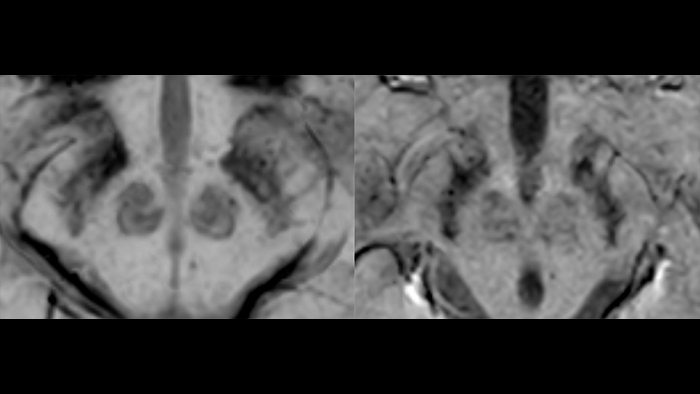

Идиопатическая болезнь Паркинсона (БП), вызванная прогрессивной потерей дофаминергических нейронов в черной субстанции головного мозга, является самым распространенным нейродегенеративным заболеванием. Нигросомы – небольшие группы дофаминергических клеток, в которых наиболее активно протекают процессы нейродегенерации. В диагностике особое внимание уделяется нигросоме-1, содержащей наибольшее количество дофаминергических нейронов. В норме на SWI изображениях она является гиперинтенсивной за счет низкого содержания в ней железа [23] - черная субстанция по форме напоминает хвост ласточки (рис.13, слева).

БП сопровождается накоплением железа в нигросоме-1 и снижением сигнала от этой области, “хвост ласточки” изменяется на “запятую” (рис.13, справа), что является маркером данного заболевания [24]. Недавнее исследование Zorzenon et al., использовавшее МР-томограф Achieva 3 Тл, с участием 62 пациентов и здоровых добровольцев показало эффективность использования этого маркера: чувствительность и специфичность составили 91% и 88% соответственно. Более того, значение коэффициента Каппа Коэна, который описывает соглашение между результатами различных экспертов, для SWIp выше, чем у T1- и Т2-взвешенных изображений. Норме соответствовал случай, когда отчетливо видна хотя бы одна из нигросом-1, положительный же диагноз ставился, если нигросома-1 не наблюдалась в одном или обоих полушариях [25]. В исследовании Zhao et al. [26] аналогичная методика использовалась для разделения пациентов с БП и сосудистым паркинсонизмом (СП). БП и СП имеют схожую клиническую картину, однако в силу различной скорости развития патологий для эффективной терапии необходимы маркеры, уникальные для одного из этих заболеваний [27]. Последовательность SWIp может стать одним из основных методов дифференциальной диагностики БП и СП. Так, в вышеупомянутой работе точность и специфичность определения БП по гипоинтенсивности нигросомы-1 (что соответствует отсутствию “хвоста ласточки”) составила 93% и 92%.